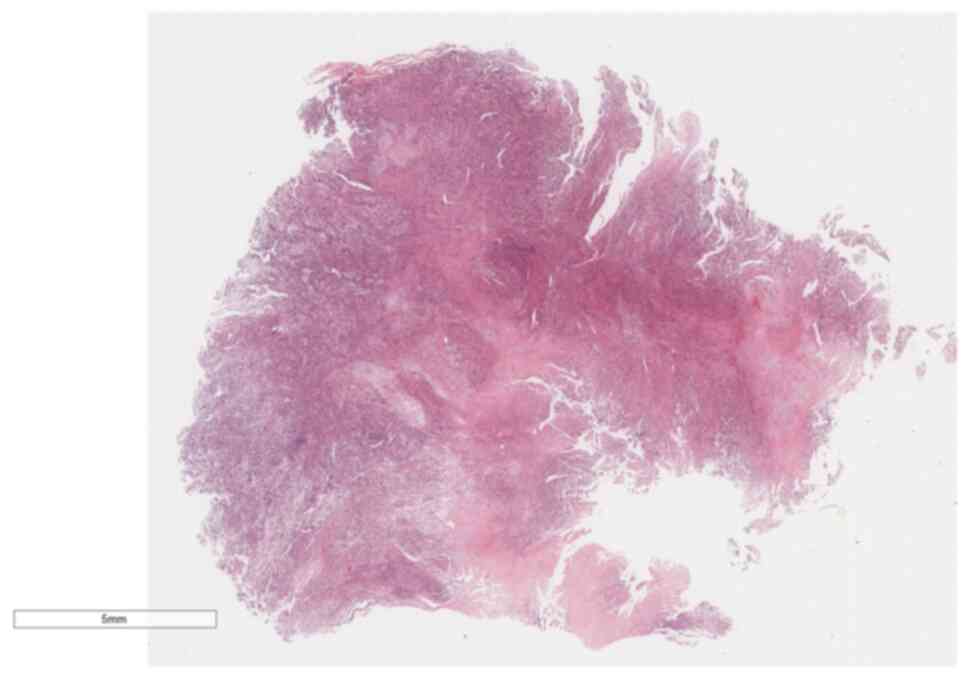

A pathological biopsy examination was performed on the lung tissue specimen, measuring 92×85×76 mm. Gross examination revealed a mass of fragmented gray-white to gray-brown tissue, ~81×72×58 mm in size (Fig. 3). The cut surface appeared gray-white and solid, with a delicate cut surface. The boundary between the mass and the surrounding lung tissue was relatively distinct, with certain areas exhibiting tight adhesion to the visceral pleura. The specimens were fixed in 4% neutral formalin at room temperature for 12 h, followed by routine dehydration, paraffin embedding and sectioning at a thickness of 5 µm. Hematoxylin and eosin staining was then performed at room temperature for 5 min each. Microscopic examination (Leica Biosystems) at low magnification revealed tumor cells diffusely distributed in sheets with high cellular density, and a few glandular-like structures were visible between the spindle-shaped solid sheets of tissue (Fig. 4). At high magnification, the solid part was composed of immature primitive embryonic components (Fig. 5), lacking malignant epithelial elements. In certain areas, embryonal rhabdomyosarcoma (ERMS)-like differentiation (Fig. 6) and immature chondrosarcoma-like differentiation (Fig. 7) were observed. The tumor cells exhibited anaplastic changes, with hyperchromatic enlarged nuclei, an increased nucleo-cytoplasmic ratio, and the presence of tumor giant cells and pathological mitotic figures.

Figure 4.

Low-power microscopy reveals that the tumor cells are diffuse and distributed with high cell density (H&E stain; magnification, ×10).